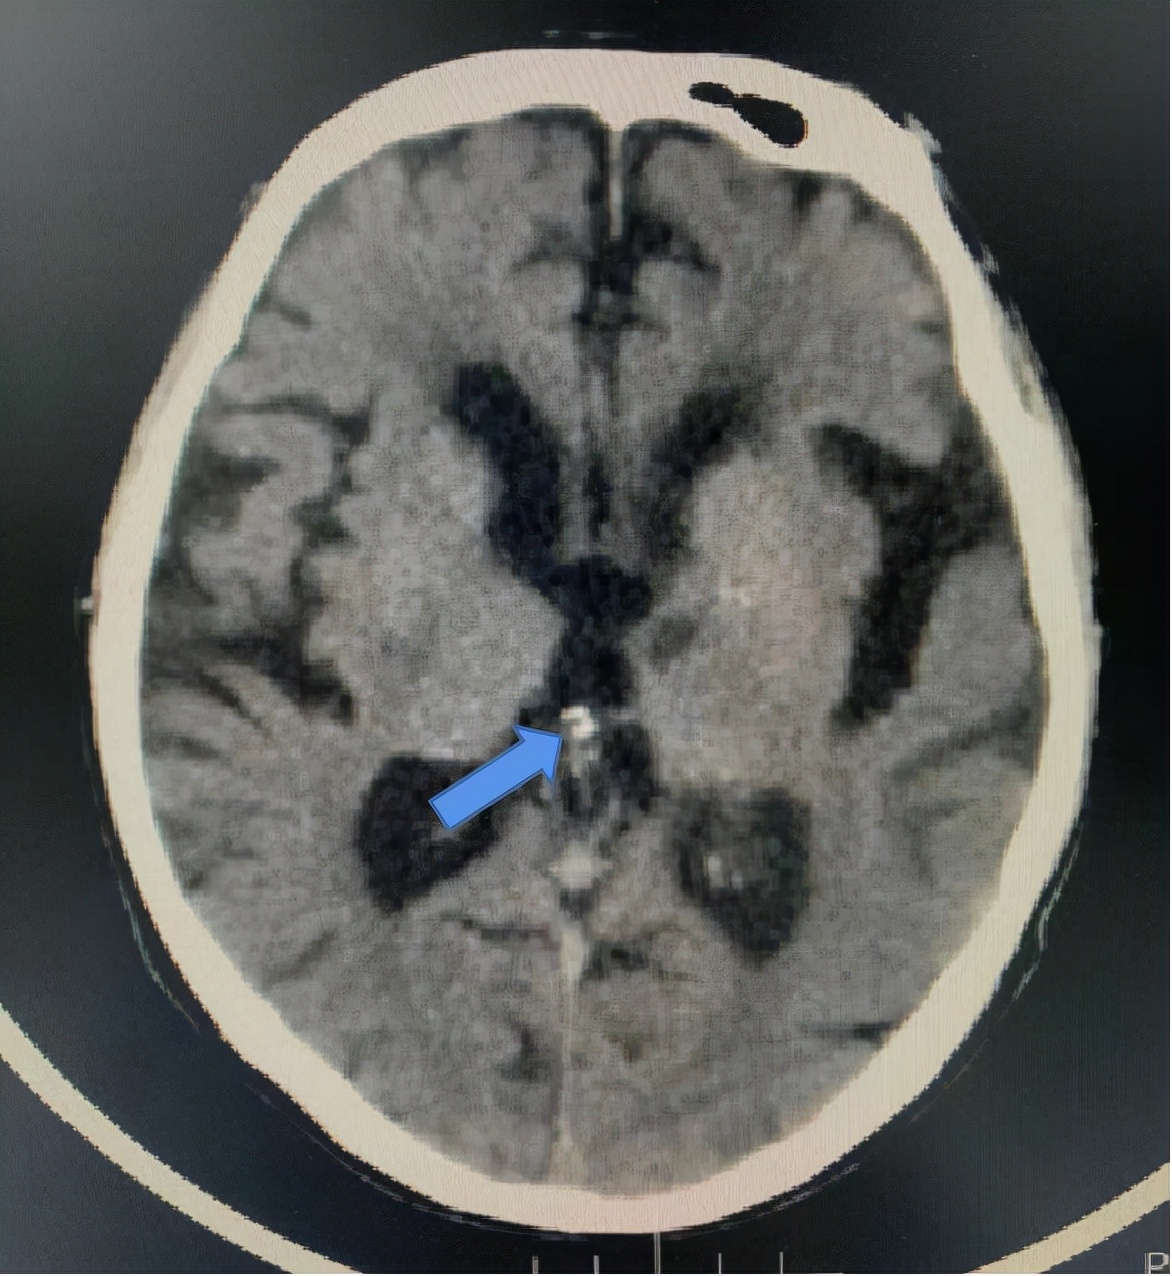

各种单发钙化灶(如肺内钙化灶)。钙化分为生理性和病理性钙化,通俗地讲,人体的某些部分就喜欢钙盐沉积,如颅内的松果体,这就是生理性的。

病理性的钙化,多种多样,可以是坏死的组织,如结核病,也可以是钙鳞代谢障碍的疾病等。比如肺内 钙化灶,其实就是可能过去得过肺炎或肺结核后钙盐沉积在坏死组织里的结果,完全不用管。

脑,松果体钙化(箭头所指,白色,结节状)。病例同时存在脑白质脱髓鞘,脑萎缩,腔梗。